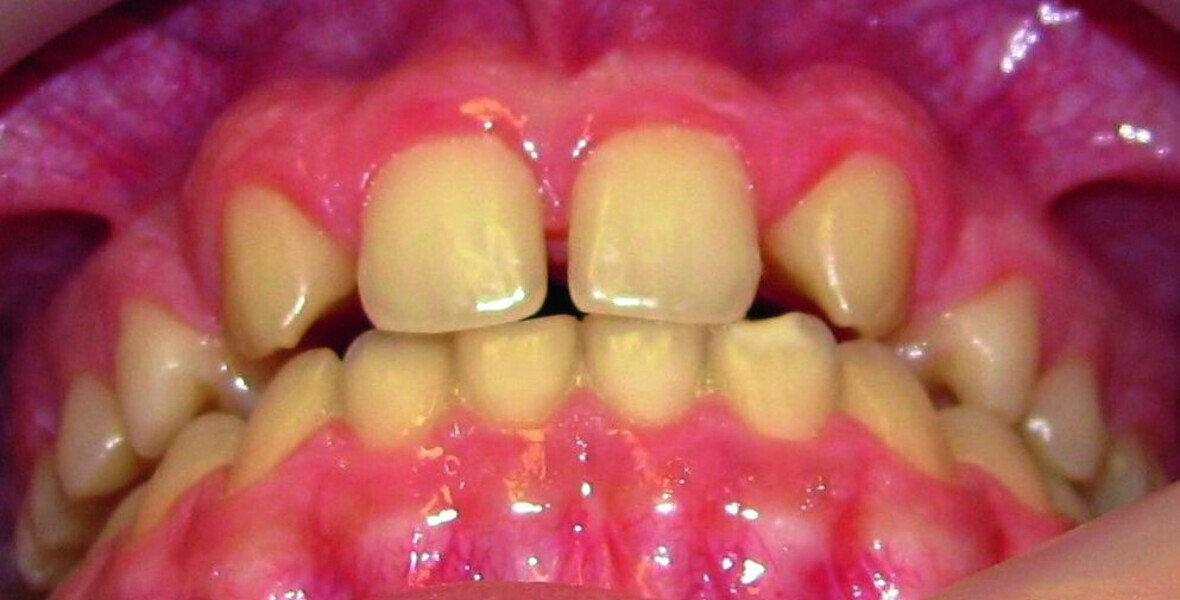

Orthodontic management of maxillary lateral incisors agenesis